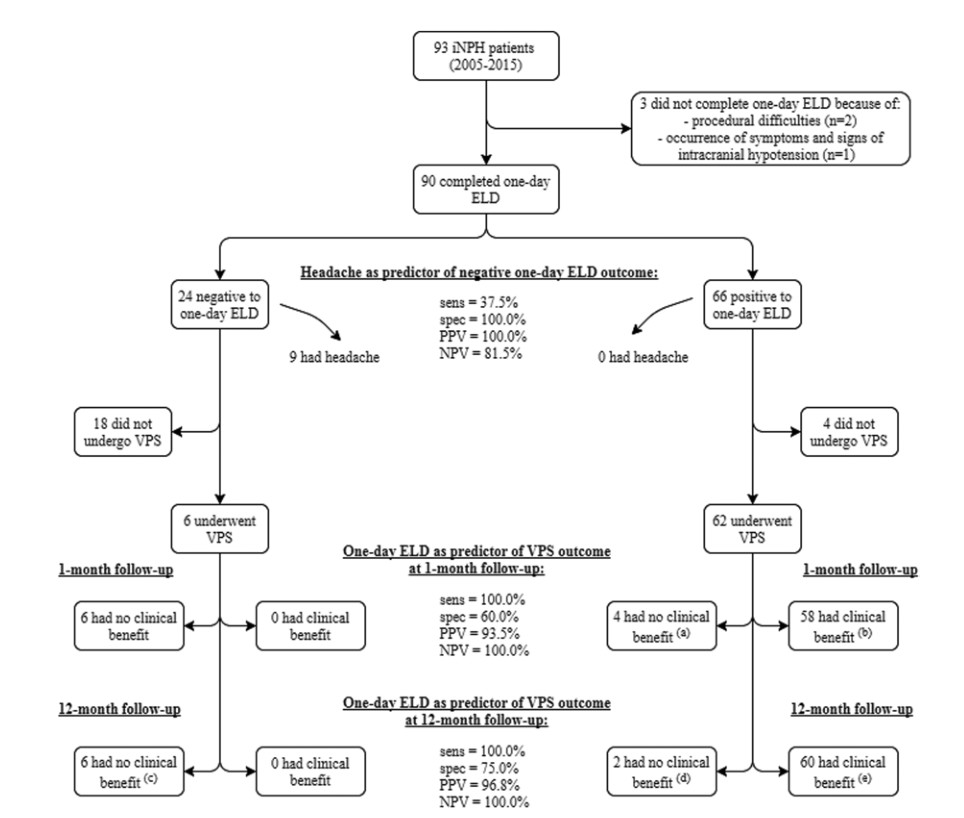

在临床上,通过在术前进行3~5天的脑脊液(CSF)腰椎外引流操作(ELD)是对特发性常压性脑积水(INPH)选择脑室腹腔分流(VPS)手术的一种常用试验。本文中,作者分析了较短(1天)ELD操作的准确性和并发症发生率。在本文中,作者回顾性分析2005年~2015年间接受1天ELD的INPH患者资料,患者选择采用带有程控分流阀的VPS手术。排除VPS并发症、分流阀功能障碍或随访不到1年的患者。通过计算敏感性、特异性和阳性预测值和阴性预测值来评估1天ELD对预测术后1个月和术后12个月随访时VPS临床获益有效与否的能力。结果,对于93例接受1天ELD治疗的患者中,3例未完成手术。在其余90例患者中,2例出现一过性神经根刺激。24名患者的测试评定为ELD阴性(放液试验阴性),66名患者的测试结果为ELD阳性(放液试验阳性)。24例ELD阴性患者中,有9例患者有术中头痛,作者把“术中头痛”作为1天ELD阴性预测结果的预测因子,其敏感性为37.5%(95%可信区间[CI]19.5%-59.2%),特异性为100%(95%CI 93.1%-100%)。68例患者(6例ELD阴性和62例ELD阳性)接受了VPS插入,在术后1个月的随访中,两组分别有0例和58例成功。术后随访1个月时检测预测手术结果的敏感性和特异性分别为100%(95%CI 92.3%-100%)和60%(95%CI 27.4%-86.3%),准确性为94.1%(95%CI 85.6-98.4%)。在1天ELD阳性的患者中,2例在术后12个月的随访中显示没有临床获益。术后12个月随访时预测手术结果的试验敏感性和特异性分别为100%(95%CI 92.5%-100%)和75.0%(95%CI 35.6%-95.5%),准确性为97.1%(95%CI 89.8%-99.6%)。结论:1天ELD是治疗INPH的可靠预测工具,并发症风险低,引流持续时间短。鉴于在术后1个月和术后12个月的随访中,成功结果的概率很高,所以该研究在预测哪类患者将通过VPS置入获得阳性结果方面非常一致;对于1天ELD阴性结果患者,VPS手术失败的风险很高。操作术中头痛为1天ELD结果为阴性的预测症状。

图:93例特发性常压性脑积水(INPH)中,90例进行了1天腰椎外引流操作(ELD)。24例ELD阴性结果患者中,6例接受了脑室腹腔分流 (VPS)手术,在术后1个月和12个月的随访中,0例获益。66例ELD阳性患者中,62例接受VPS手术,在1个月随访中,58例临床获益;在12个月随访中,60例临床获益。操作术中头痛为1天ELD结果为阴性的预测症状。